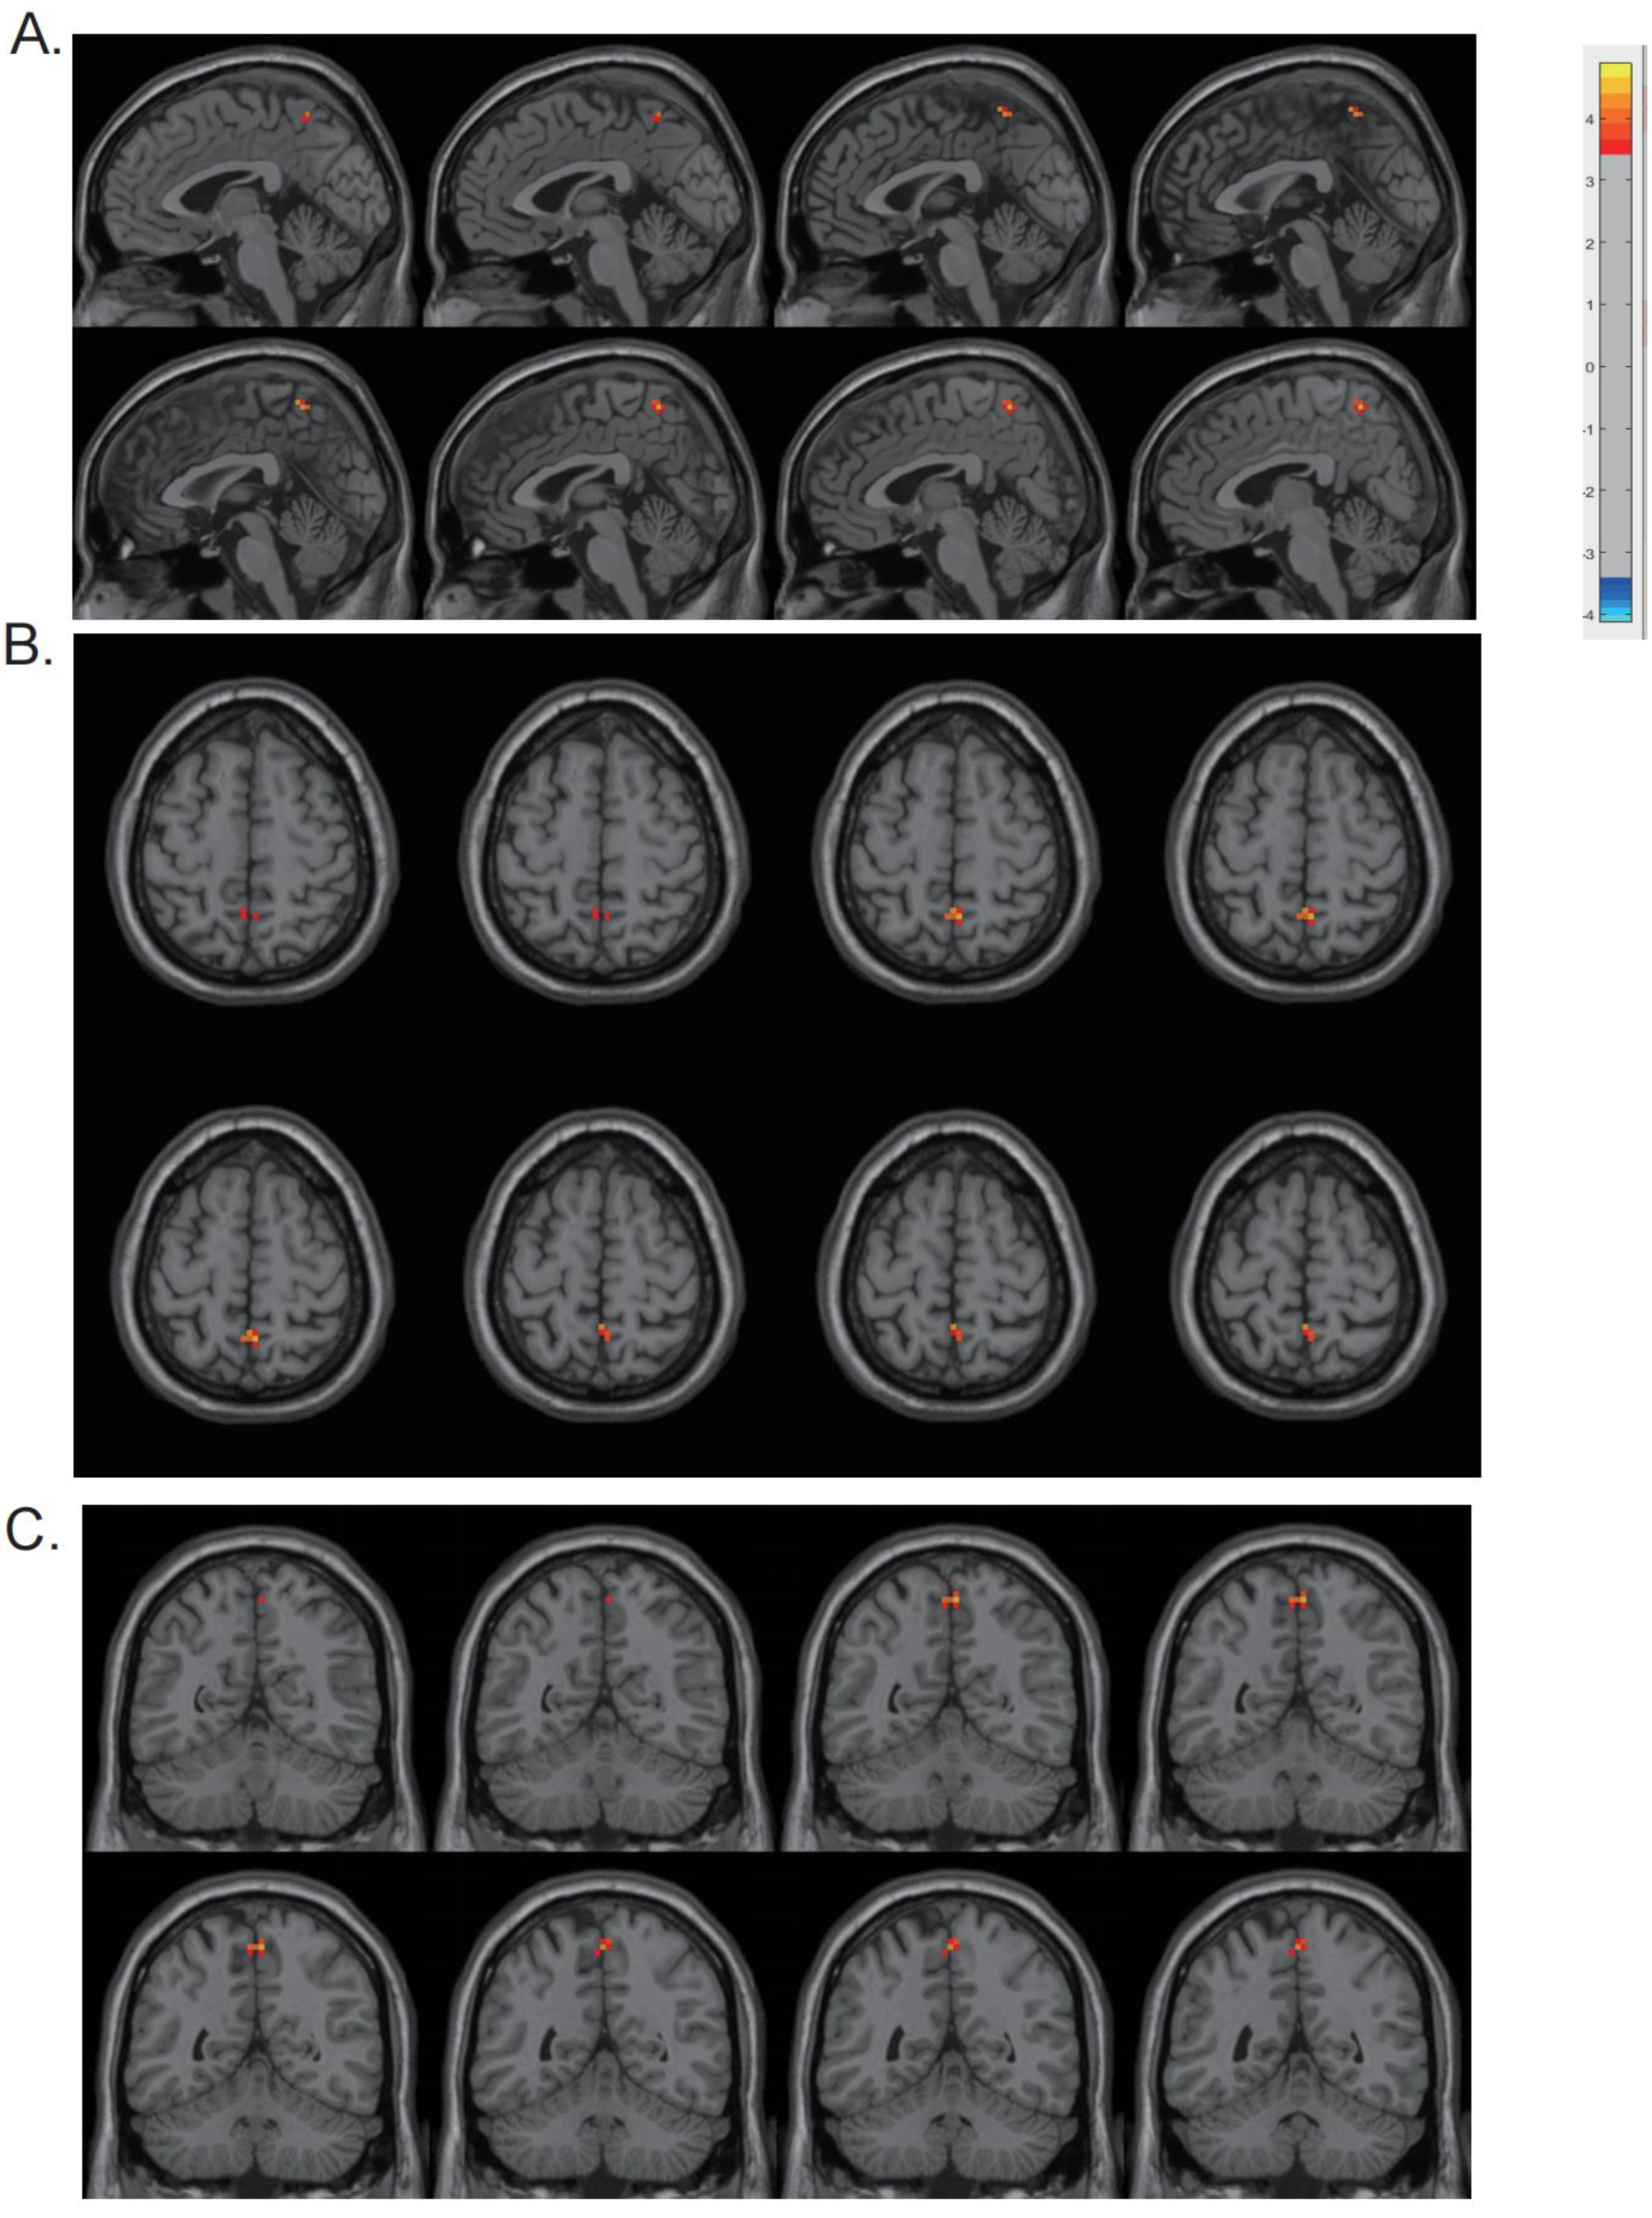

3.3. DReHo Analysis and Correlation Analysis

| Region | Cluster Size (Voxel) | MNI (x, y, z) | t-Value |

|---|---|---|---|

| Precuneus | 13 | (3, −54, 60) | 4.5626 |